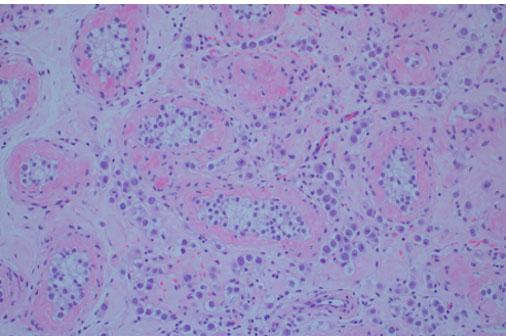

A simple bilateral orchiectomy was performed via a scrotal approach without complication, and the specimens were sent to pathology per routine protocol. Histology identified a subtle, 1.0 cm seminoma with intertubular growth (Figure 4) and associated germ cell neoplasia in situ (GCNIS). Given the atypical growth pattern, the morphologic impression was confirmed with OCT3/4 immunohistochemical stain, demonstrating strong staining in both seminoma and GCNIS (Figure 5). Grossly, the specimens were unremarkable.

Figure 4: Seminoma (pure), with intertubular/interstitial growth pattern and germ cell neoplasia in situ. Background of tubular atrophy and peritubular hyalinization seen in GAHT treatment, H&E 400×.

Figure 5: OCT3/4 immunohistochemical stain demonstrating interstitial pattern, OCT3/4 100×.